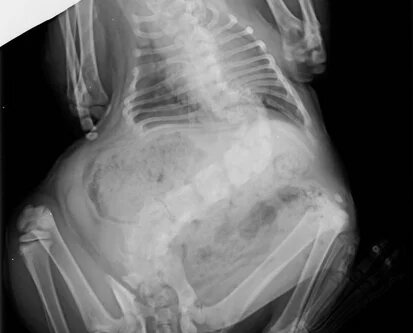

Przy badaniu lekarz podejrzewał, że zwierzę ma problemy poważniejsze niż nadwaga. Zdjęcia rentgenowskie potwierdziły ciężki stopień skoliozy, w wyniku czego ciało kota wygięło się.